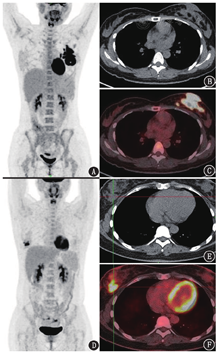

由于奥美定的这些不良事件,2006年我国撤销了其医疗器械注册证。虽然奥美定及相关并发症在现今的影像检查中已不多见,但实际上乳房假体本质上都是异物,如果异物没有被包膜限制住而流入组织间隙,都有可能产生类似的异物巨细胞反应。如图2患者(女,46岁),体格检查发现右腋下淋巴结肿大2周,7年前行双侧乳房假体植入术,近期超声示右乳房假体包膜欠光整,透声欠佳,右侧腋窝肿大淋巴结。18F-FDG PET/CT显像可见右侧腋下、右侧锁骨下、右侧内乳淋巴链区多发代谢增高淋巴结,最大者长径2.0 cm,SUVmax为12.0,另外右上纵隔也可见代谢增高淋巴结;乳腺可见双乳假体植入,右乳外下象限可见小结节,长径0.9 cm,SUVmax为2.7(图2)。这种情况首先要考虑到右侧乳腺癌(或隐匿性乳腺癌)伴同侧引流区淋巴结转移的可能;但若再仔细观察图像并结合病史中超声提示的右乳假体包膜欠光整、透声欠佳的表现,可以发现右乳假体包膜周围的软组织影较左侧略增厚,部分区域包膜不光整,并且右侧假体包膜周围的代谢更高,提示存在右乳假体破裂的可能。如果存在乳房假体破裂,可以形成硅胶颗粒并沿组织间隙或淋巴道扩散,炎性反应与异物巨细胞反应可表现为高代谢。此患者之后行2次右腋下淋巴结活检,病理均未提示肿瘤,之后再行双侧乳房假体取出术,术中见右乳假体包膜有破裂。此后患者每年复查超声乳腺未见明确异常,所以PET/CT所见的右侧腋下及锁骨下、右侧内乳淋巴链区及上纵隔的代谢增高淋巴结,考虑均为右乳假体破裂所致的引流区炎性淋巴结及异物肉芽肿。